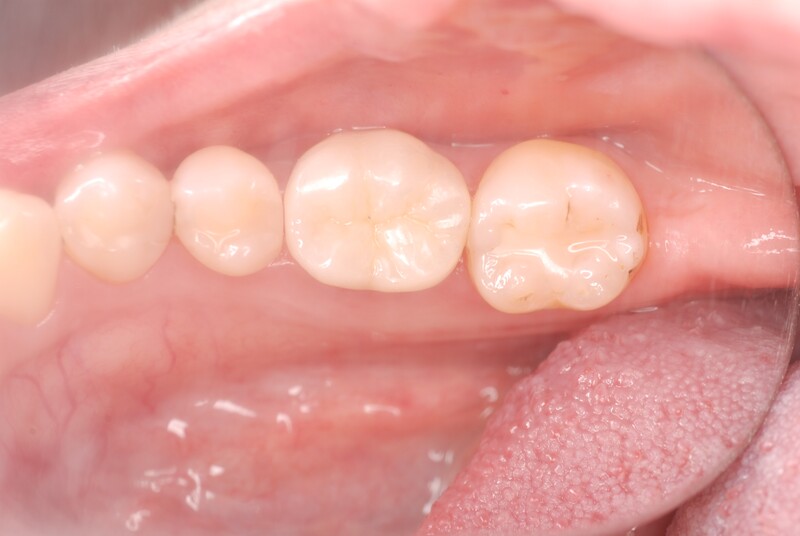

状態が改善したことを確認し、最終的な被せ物を装着しました。